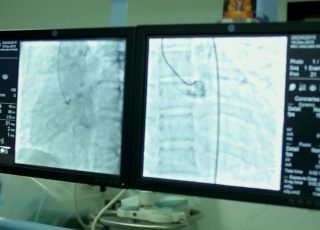

Coronary angiography is a procedure in which a contrast material which can be seen using specialised equipment, is injected into one of the arteries of the heart.

This allows the observation of the blood flow through the heart to detect blockages in arteries. An intravenous line is inserted into one of the blood vessels in the arm or groin area. A catheter is then inserted through the IV which is carefully guided into the heart using an x-ray machine that produces real-time pictures. Once the catheter is in place, a contrast material is injected and images are taken giving the cardiologist a true picture of the region in which arterial blockages lie.The number of blockages and the extent of damage can also be ascertained.